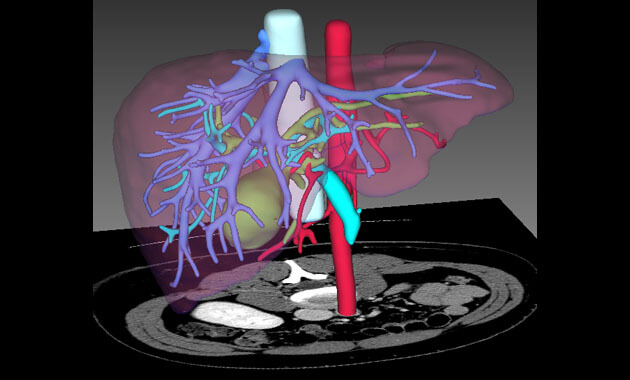

The Abdominal Imaging Division of the UC San Francisco Department of Radiology and Biomedical Imaging is made up of internationally recognized abdominal imaging experts who diagnose and treat disorders of the liver, pancreas, colon, uterus, ovaries, prostate, and bladder. The Abdominal Imaging Division is focused on serving patients, conducting research, and training the next generation of radiologists.

- Liver disease/transplants